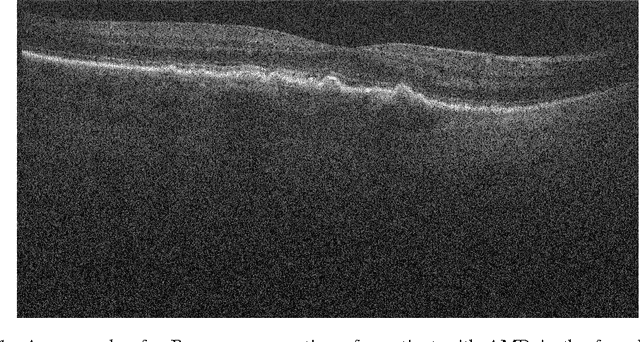

Abstract:Optical Coherence Tomography (OCT) provides a unique ability to image the eye retina in 3D at micrometer resolution and gives ophthalmologist the ability to visualize retinal diseases such as Age-Related Macular Degeneration (AMD). While visual inspection of OCT volumes remains the main method for AMD identification, doing so is time consuming as each cross-section within the volume must be inspected individually by the clinician. In much the same way, acquiring ground truth information for each cross-section is expensive and time consuming. This fact heavily limits the ability to acquire large amounts of ground truth, which subsequently impacts the performance of learning-based methods geared at automatic pathology identification. To avoid this burden, we propose a novel strategy for automatic analysis of OCT volumes where only volume labels are needed. That is, we train a classifier in a semi-supervised manner to conduct this task. Our approach uses a novel Convolutional Neural Network (CNN) architecture, that only needs volume-level labels to be trained to automatically asses whether an OCT volume is healthy or contains AMD. Our architecture involves first learning a cross-section pathology classifier using pseudo-labels that could be corrupted and then leverage these towards a more accurate volume-level classification. We then show that our approach provides excellent performances on a publicly available dataset and outperforms a number of existing automatic techniques.